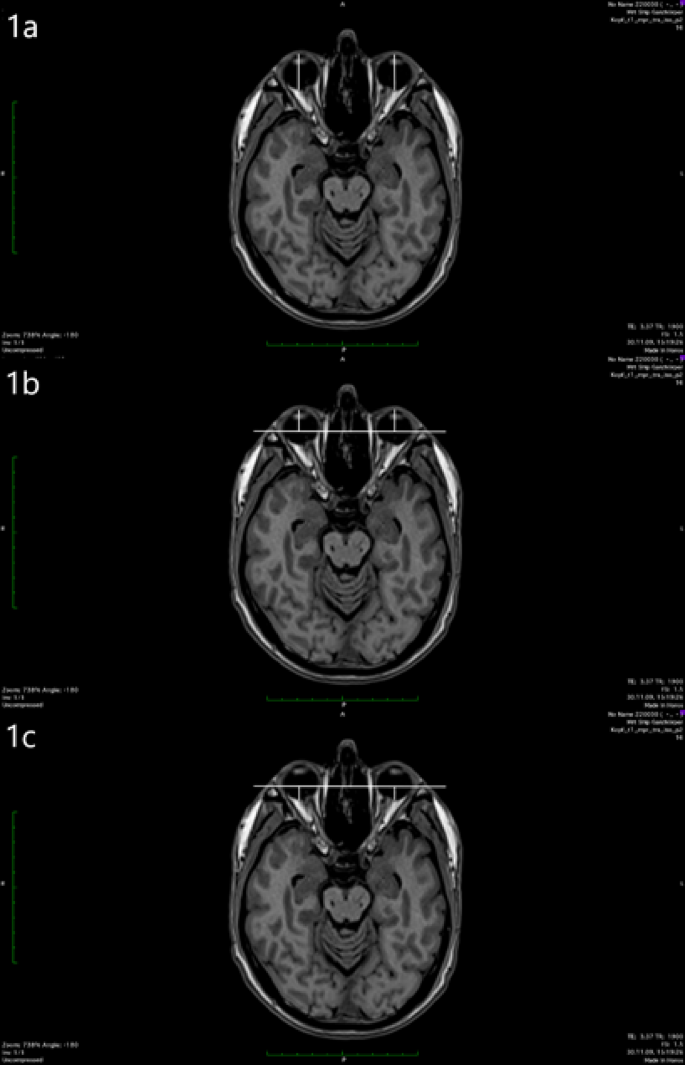

The length of the eye ball was measured between the posterior surface of the cornea, which was better visible on MRI images than the anterior surface, and the posterior pole of the ocular globe (Fig. 1a). The measurement was repeated for several scans. The maximum value determined from all measurements corresponded to the bulbar axial length. The selected image plane was chosen for all further measurements on both eyes. For exophthalmometry, a connecting line was drawn between the lateral bony boundaries of the orbits. This line, also known as the interzygomatic line, lies on the bony orbital margins without intersecting them. Anterior exophthalmometry is measured from the posterior surface of the cornea at the level of the corneal apex, starting from the interzygomatic line (Fig. 1b). Posterior exophthalmometry is performed accordingly between the interzygomatic line and the posterior pole at a 90° angle (Fig. 1c). The corresponding flowchart illustrating the study design is shown in Fig. 2.